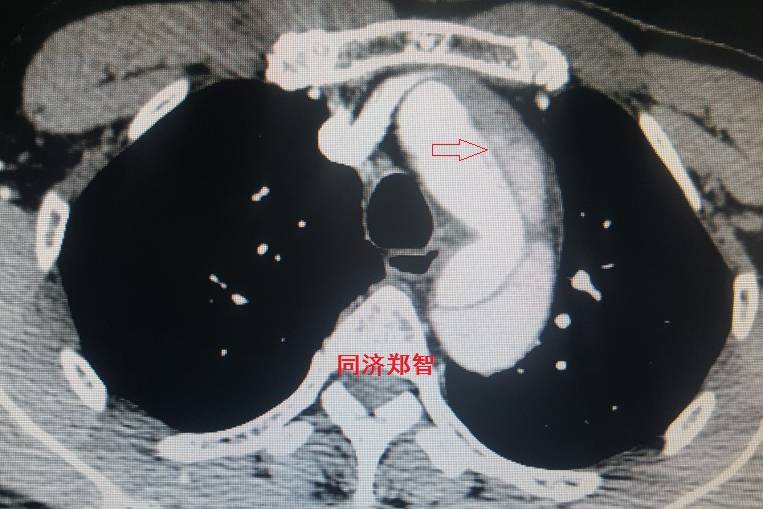

平扫CT提示主动脉弓层面及右肺动脉层面均可见主动脉血管腔内的内膜片影(红色箭头所示),CTA显示为A型主动脉夹层。